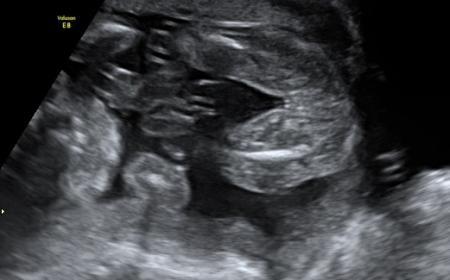

Hallo ihr! Ich bin zurück vom zweiten großen Ultraschall. Es ist alles gut :-) Es wird ein Mädchen werden, was ja aber schon zwei andere Ärzte bestätigt haben. In zwei Wochen geht es noch zum Fein-Ultraschall. Mein Arzt meint, er ist dann beruhigter, weil ich ja gern daheim entbinden möchte. Hat das jemand machen lassen von euch und weiß wie viel das kosten wird, oder ob das die private Krankenversicherung zahlt? Ich häng euch mal noch zwei Bildchen an :-) Auf dem einen macht sie grad ne Spucke-Blase und auf dem anderen, sieht man mal wieder überdeutlich, dass es ein Mädchen wird (ich hoffe ihr erkennt das auch :-) ) Bin echt froh, dass alles gut ist. Nächste Woche geht es wieder in die Schule, dann schauen wir mal, wie es mir da geht.

Hier noch das zweite Bild :-)

Also man erkennt klar und deutlich das es ein Mädel wird.